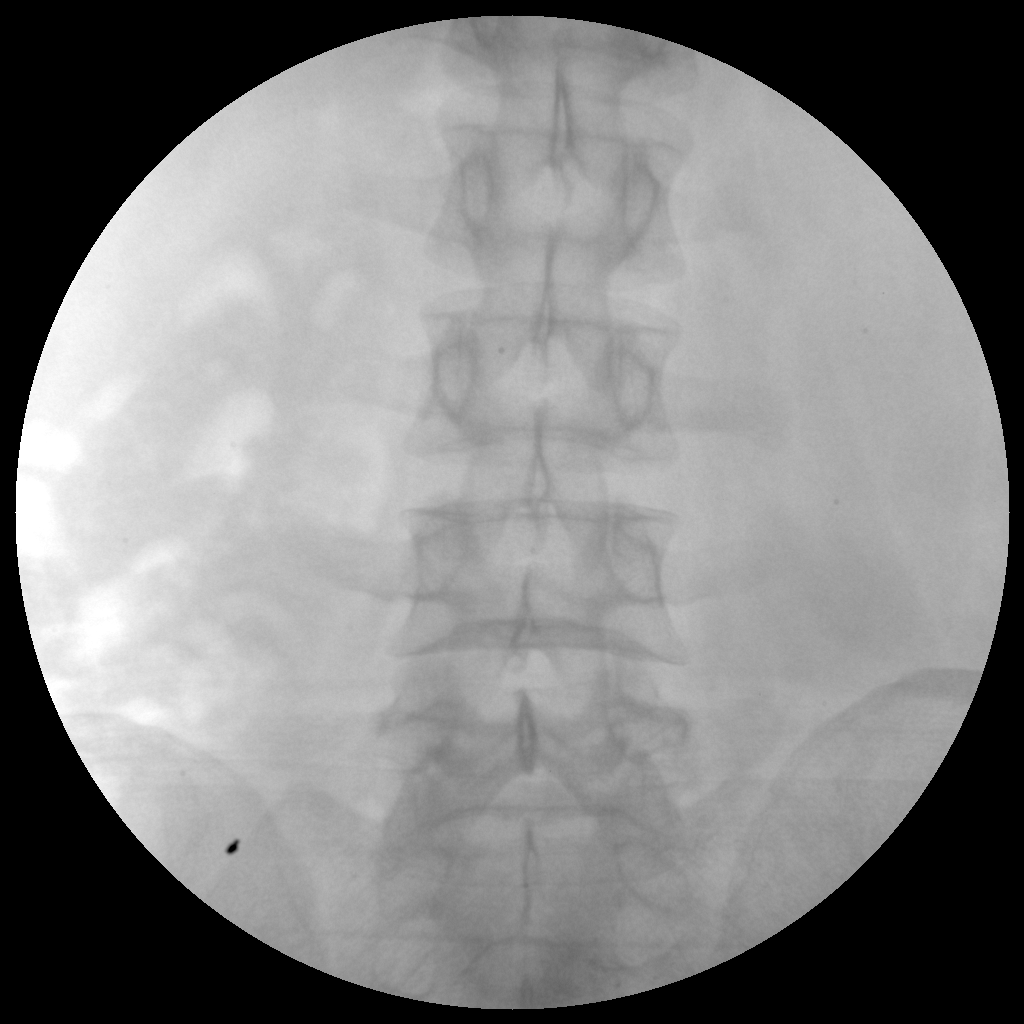

Clinical picture

臨床圖片